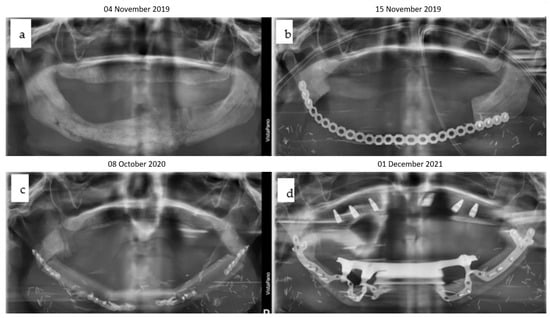

Figure 5. (ad): Four orthopantomograms depict the dental rehabilitation sequence, commencing with the insertion of the IPS Implants® Preprosthetic (KLS Martin-Group, Tuttlingen, Germany) (a); subsequently, the positions for the three bone-level tapered implants were drilled in a 3D-guided manner in a second step (b). During recall, the final bar-retained suprastructure (c) is visible, as well as at the three-year follow-up (d). No bone loss or screw loosening is evident. The key distinction between conventional implants and IPS Implants® Preprosthetic anchorage is apparent: unlike conventional implants, where anchorage relies on multivector screw-based fixation near the area equivalent to the dental implant shoulder, the IPS Implants® Preprosthetic constitutes a one-piece implant with a rotationally stable telescoping abutment component.